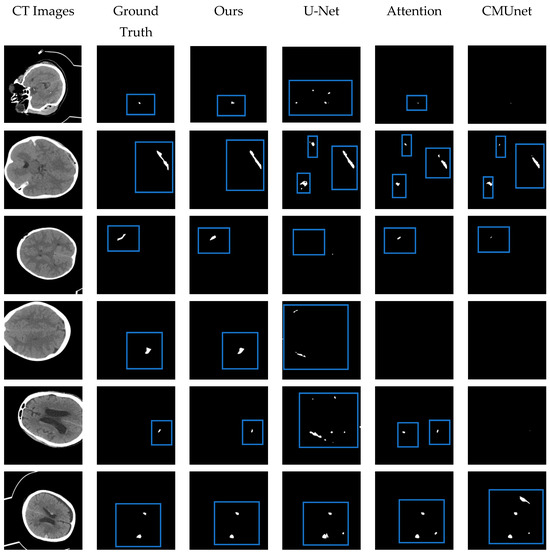

4.5. Comparison with Other Methods

| Name | Dice | Jaccard | Sensitivity | Precision |

|---|---|---|---|---|

| Hssayeni et al. [32] | 0.315 | 0.218 | ||

| U-Net [25] | 0.610 | 0.491 | 0.644 | 0.632 |

| Attention U-Net [27] | 0.645 | 0.529 | 0.667 | 0.676 |

| CMUNet [40] | 0.666 | 0.547 | 0.656 | 0.707 |

| Ours | 0.717 | 0.596 | 0.779 | 0.712 |